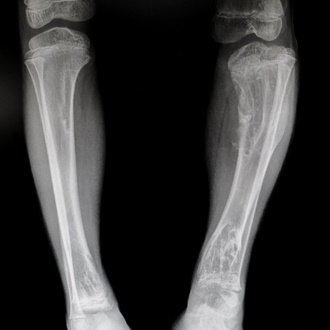

| Рентгенография шейного отдела | Это основной метод для подтверждения диагноза. Снимки в нескольких проекциях (прямой, боковой, с функциональными пробами) позволяют увидеть сросшиеся позвонки, оценить их количество и локализацию, выявить нестабильность позвоночных сегментов. |